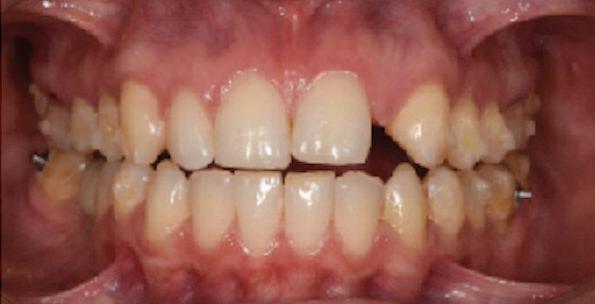

Dental Tribune Bulgarian Edition / октомври 2022 г.16 клиничен случай с алайнери Г орният латерален ре зец е вторият найчесто вродено липсващ зъб.1,2 Поради разполо жението му във видимата зона на усмивката лечение то на подобни случаи нала га мултидисциплинарен под ход, целящ отличен функцио нален и естетичен резултат. Налице са няколко лечебни мо далности, свързани с различ но разпределение на място то: първият вариант е орто донтско отваряне на място и възстановяване на липсва щия зъб с конструкция, под държана от съседните зъби3 или от имплант4, докато при втория подход разстоянията се затварят и премоларът заема мястото на канина.5 Изборът на лечебен подход трябва да бъде направен съв местно от зъболекар и паци ент въз основа на очакванията на последния и предвиди мостта на лечението. Множе ство фактори влияят върху това решение, като напри мер типа малоклузия, размера, формата и цвета на кучеш ките зъби6, оклузалните вза имоотношения (овърджет и овърбайт), лицевия профил, дължината на зъбната дъга и несъответствията в разме ра на зъбите.7 В настоящата публикация се разглежда случаят на жена в зряла възраст с вродена лип са на горен ляв латерален резец. Бяха приложени про зрачни алайнери за отваряне на място за единичен им плант и бяха постигна ти функционална оклузия и отлична естетика. ПРЕДСТАВЯНЕ НА СЛУЧАЯ Диагноза Пациентката бе на 32 годи ни, когато лечението започна, и първоначалното ѝ състоя ние бе следното (фиг. 1–3): липсващ горен ляв латерален резец; клас II, подклас I малоклузия; отклонение на горната сре динна линия вляво; Доклад на клиничен случай ЛЕЧЕНИЕ С АЛАЙНЕРИ НА ПАЦИЕНТ С АГЕНЕЗИЯ НА ЛАТЕРАЛЕН РЕЗЕЦ Д-р Iro Eleftheriadi и д-р Christodoulos Laspos, Гърция и Кипър Фиг. 1a–h Предоперативни лицеви и интраорални снимки. Фиг. 2a–e Дигитални модели преди началото на лечението. Фиг. 3 Панорамна снимка преди лечението. Фиг. 1a Фиг. 1d Фиг. 1f Фиг. 2a Фиг. 2d Фиг. 2b Фиг. 2e Фиг. 3 Фиг. 2c Фиг. 1b Фиг. 1e Фиг. 1g Фиг. 1h Фиг. 1c

Dental Tribune Bulgarian Edition / октомври 2022 г. 17клиничен случай с алайнери леко струпване в долната че люст; несъответствие по Болтън (мандибуларен излишък от 3.06 мм във фронталната зона и общо 1.47 мм); издължено лице с лицева аси метрия; конвексен профил с ретруди рана долна челюст и проми нентен нос. На мястото на зъб #46 бе на лице имплант, а зъби #16 и 26 са ендодонтски лекувани. Тези зъби бяха асимптоматич ни, затова бе взето решение да се прави релечение само при нужда. Мъдреците липсваха. Анализът на телерентгеногра фията (фиг. 4) показа ретрог натна мандибула (SNB: 74.2°) и нормална инклинация на резците както в

Цели на лечението и лечебен план Целите на лечението бяха следните: нивелиране и подреждане на зъбите и в двете зъбни дъги; отваряне на пространство за липсващия латерален резец; коригиране на отношенията при канините и моларите до клас I; и корекция на отклонението на срединната линия. Лечебният план включваше: корекция на отношенията при кучешките зъби и мола рите до клас I с дистализира не на максилата; отваряне на пространство в областта на #22 за поставя не на единичен имплант; корекция на срединната ли ния; и създаване на място за раз ширяване на зъб #12 и апрок симална редукция в долната челюст с цел подобряване на несъответствието по Болтън и осигуряване на подобра оклузия. Изпълнение на лечебния план Този случай бе изпълнен със системата за алайнери Invisalign (Align Technology). Одобреният първоначален лечебен план предвиждаше 49 алайне ра с дистализиране на задни те горни зъби до клас I (прибли зително с около 3.5 мм; фиг. 5). За бъдещия имплант в областта на липсващия латерал бе планирано пространство от 6.5 мм, докато във фронталния сегмент на долната челюст бе предвидена апроксимална редук ция. В дясната страна бутон за ластици клас II бе поставен на зъб #47 вместо на зъб #46, за да не се увреди короната на импланта. Понеже пациентката жи вееше в чужбина,

следните казуси: недобра оклу зия в дисталните зони по вре ме на дистализирането на гор ната челюст и накланяне на зъб #21 (фиг. 7). Последното се дължи на липсата на компози тен атачмънт на този зъб, каквото не бе зададено в пър Фиг. 4 Телерентгенография и цефалометричен анализ преди началото на лечението. Фиг. 5a–e Одобреният първоначален лечебен план. Фиг. 6a–h Снимки по време на лечението, показващи нуждата от внасяне на някои корекции. Фиг. 4 Фиг. 5a Фиг. 5d Фиг. 6a Фиг. 6d Фиг. 6f Фиг. 6b Фиг. 6e Фиг. 6g Фиг. 6h Фиг. 6c Фиг. 5e Фиг. 5b Фиг. 5c

планта бе поставена временна коронка (фиг. 10 и 11), докато бъде изготвена окончателна та. Бе постигнат отличен кра ен резултат. Меките тъка ни около импланта напълно заздравяха, което доприне се за перфектната хармония между бяла и розова естетика (фиг. 12–15).

Dental Tribune Bulgarian Edition / октомври 2022 г.18 воначалния план. Тези пробле ми бяха адресирани чрез допъл нителна поръчка на алайнери с торк контрол и зададено екст рудиране на задните зъби с цел установяване на добри оклузал ни контакти в дисталните об ласти, като бяха предвидени и оптимизирани атачмънти с контрол над корените за корекция на ангулацията на макси ларните резци (фиг. 8). Резултати от лечението Панорамната рентгено графия след ортодонтското лечение показа благоприятна паралелна позиция на съседни те зъби, подходяща за поставя не на имплант в областта на #22, както и конвергенция на ко рените на зъби #44 и 45 (фиг. 9), но преценихме, че няма да от деляме допълнително лечебно време за коригирането ѝ поради факта, че пациентката бе мно го доволна от постигнатия до момента резултат. След при ключване на лечението бяха постигнати отлични взаимо отношения клас I при мола рите и канините, а срединни

съвпадаха. Върху им

(LFH: 56.5 mm) и размерите на меките тъка ни останаха непроменени. На клонът на горните резци бе за пазен (Ui–FH: 115.8°), а долните резци бяха леко наклонени ве стибуларно (Li–APog: 30°; фиг. 16). ДИСКУСИЯ Липсата на зародиш на по стоянен горен латерален резец е налице при 3.5–6.5% от евро пеидната раса, като при жени е по-честа, отколкото при мъ жете в съотношение 3:2.8–10 Възможни са няколко лечебни подхода, включително замя ната му с преоформен канин, отваряне на място чрез орто донтско лечение и протетич но възстановяване, както и ав тотрансплантация. Устано вено е, че изборът за затваря не на място или за отваряне то му все още подлежи на дис кусия сред ортодонти и проте зисти.11,12 Според литературните дан ни затварянето на простран ството и замяната на липсва щия латерал с канин се предпо чита в случаи на едностранна липса на зародиш, балансиран профил, кучешки зъби и премола ри със сходна форма и цвят, дву челюстна протрузия или клас II малоклузия.13–15 Отваряне на пространство по-често се изби ра при клас I, наличие на диасте ми и треми в горната зъбна дъга или голяма разлика в размерите на канини и премолари.16 Скорошно проучване е уста новило, че изборът на лечение при конгенитално липсващ ла терал е пряко свързан със след ните фактори17: възрастта на пациента при започване на лечението; индивидуалните особености при всеки конкретен случай; и сътрудничеството между специалистите в лекуващия екип. Макар да има проучвания, фа воритизиращи леченията със затваряне на място11,18, всеки случай трябва да бъде оценяван индивидуално. В презентирания в тази статия случай бе взето решение за отваряне на мяс то и протетично възстановя ване, понеже целта бе да се по стигнат клас I отношения при канините и моларите, както и по-широка усмивка. За да се из бегнат компромиси, след лече нието бе постигнат клас I при моларите и кучешките зъби, несъответствието по Болтън бе подобрено и срединната ли ния бе коригирана. Други изслед вания демонстрират отлични естетични и функционални ре зултати при лечение с отваря не на място и протетична ре хабилитация.19 И двете лечеб ни модалности са подходящи за третиране на вродена лип са на зародиш на латерал и да ват сходни функционални и па родонтални резултати20, като при едно проучване